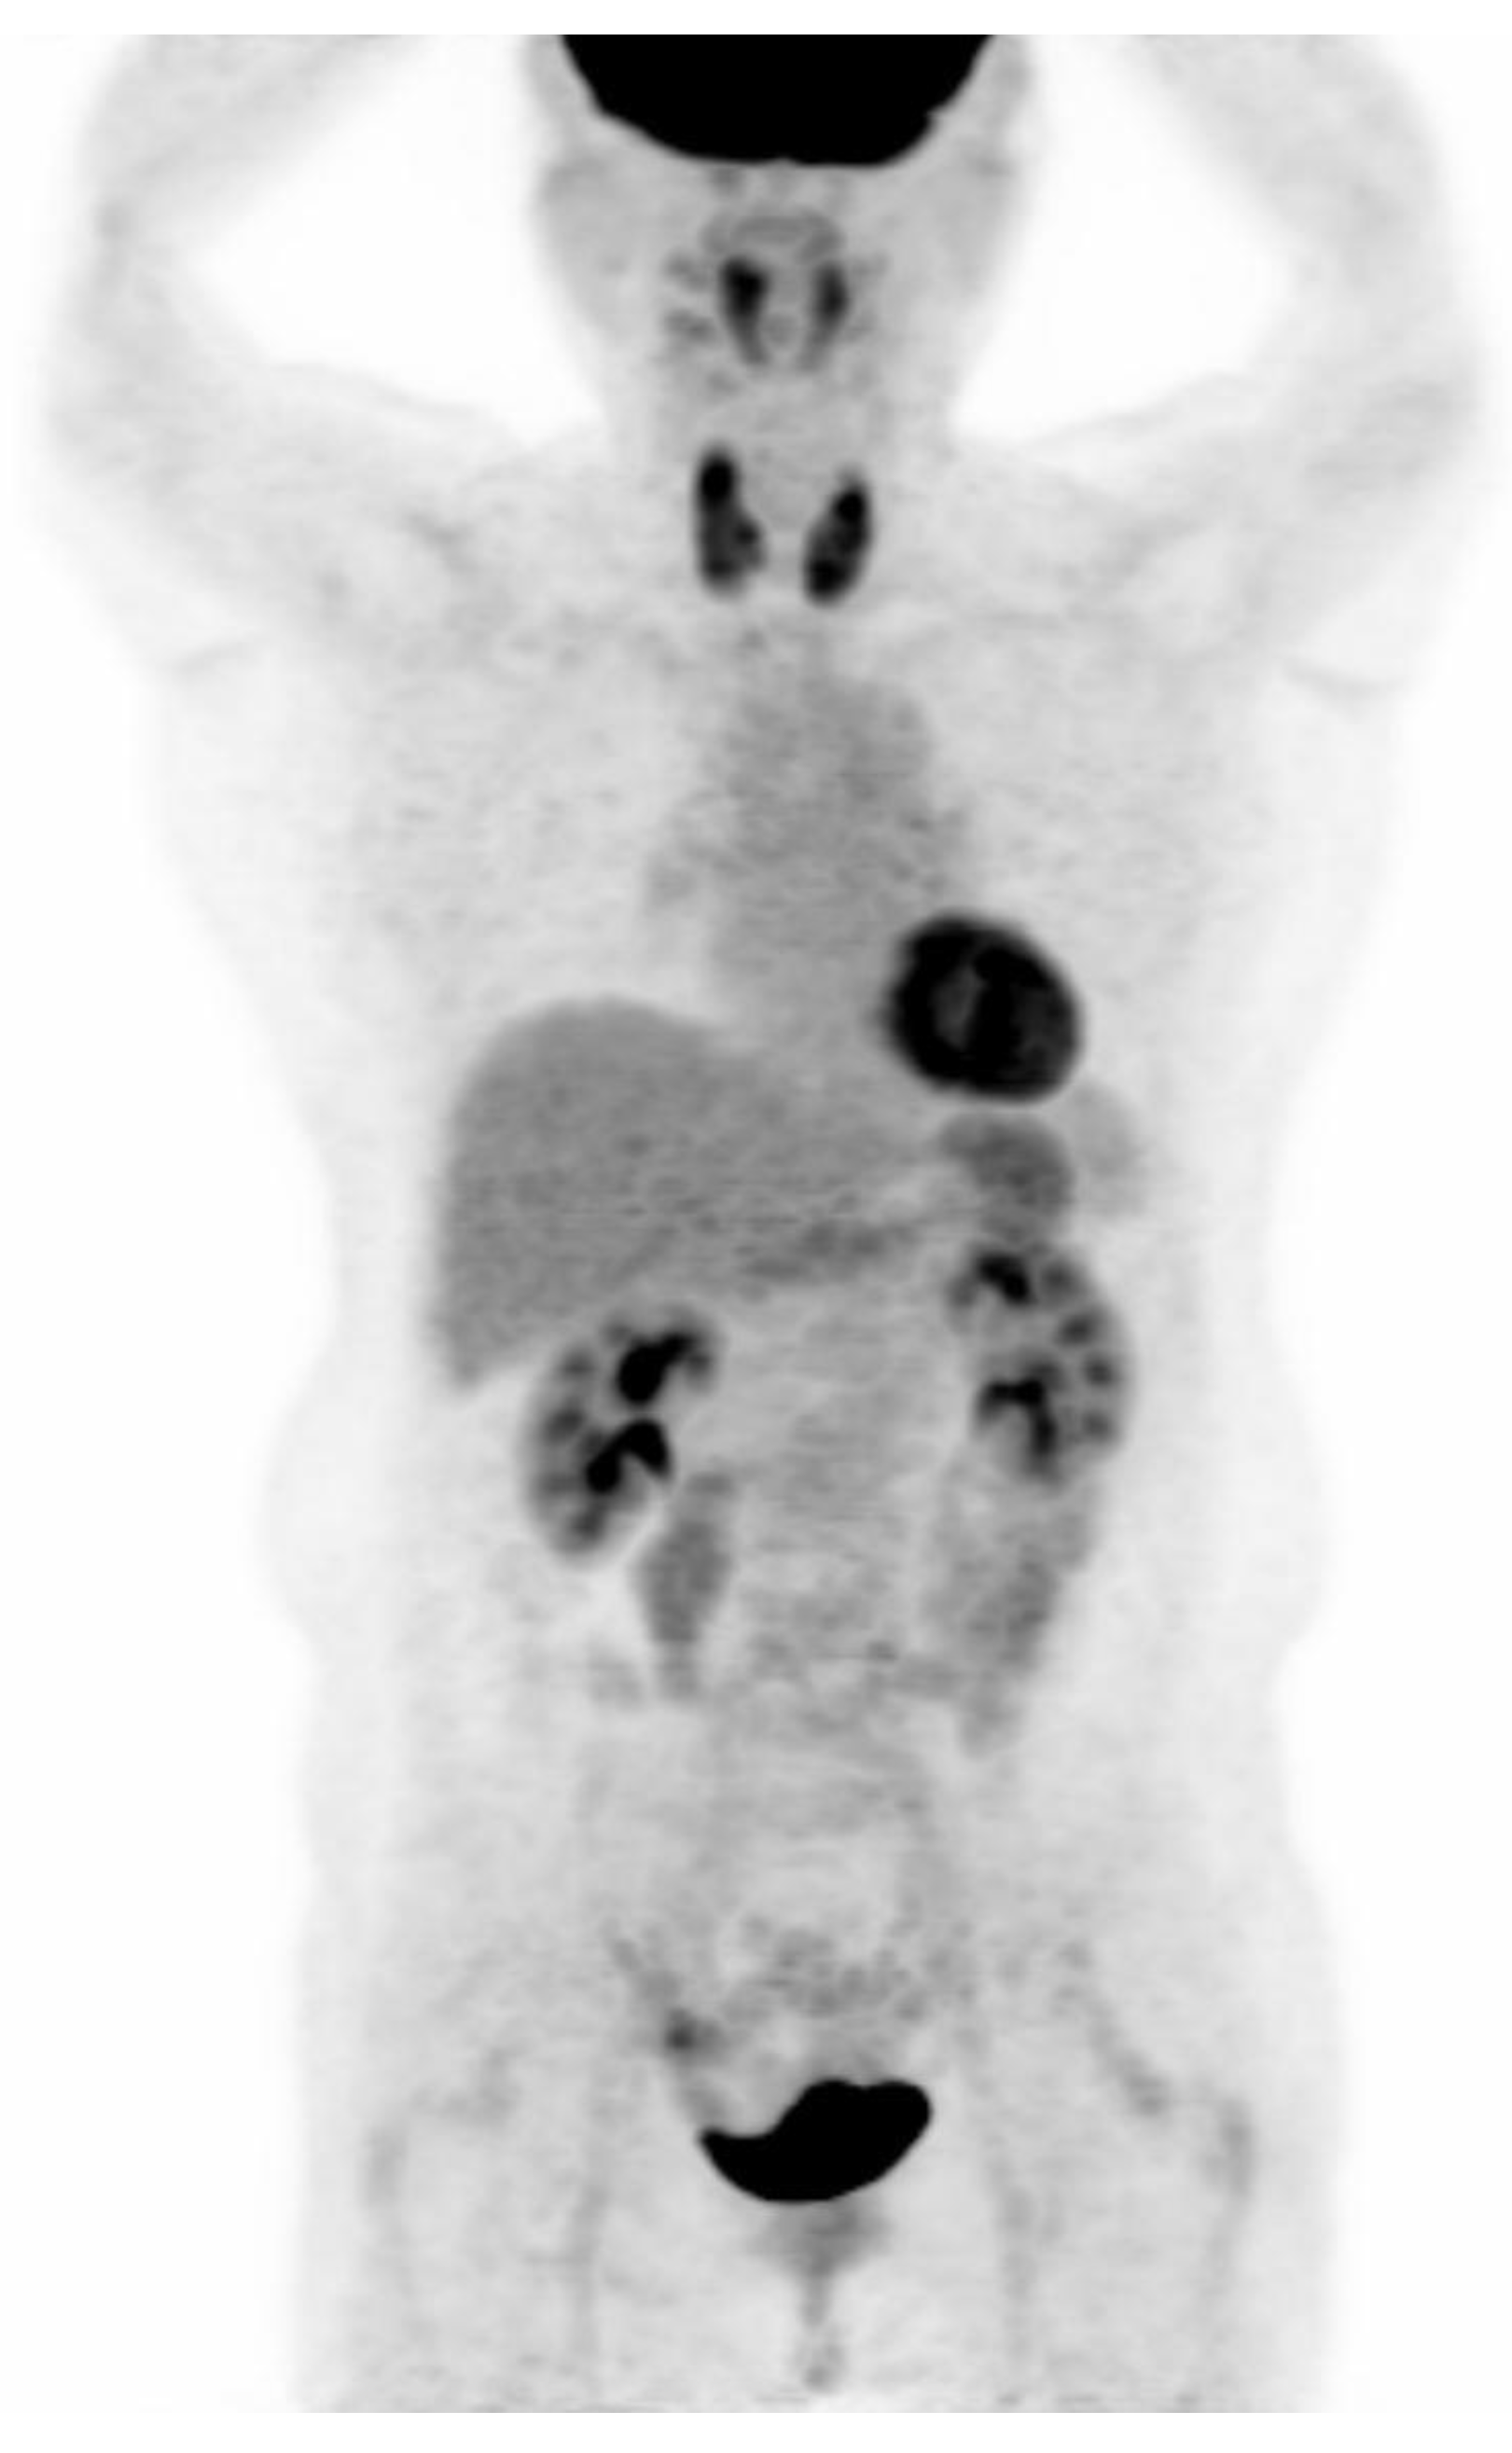

PET-CT images were interpreted by two board-certified nuclear medicine physicians who were blinded to the aim of the present study. The intensity level was set manually, with liver being set at a light-gray level. Distinct 18F-FDG uptake by the thyroid compared to the surrounding cervical background activity resulting in visualization of both thyroid lobes on three-dimensional maximum-intensity-projection (MIP) images was used as a criterion for diffuse thyroid uptake (Figure 2).

Figure 2.

Visualization of both thyroid lobes in three-dimensional maximum-intensity-projection (MIP) images which was used as a criterion for diffuse thyroid uptake.